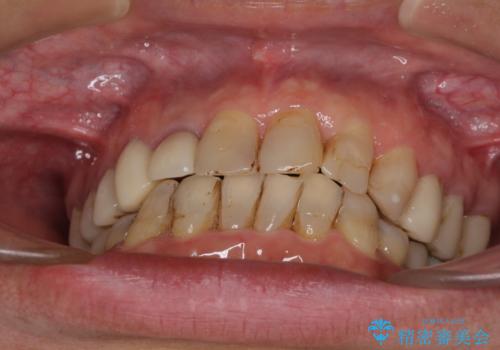

- 前歯のデコボコや、奥歯を咬んだときに痛みがあるとのことで来院された患者様です。

全体的に問題が多く、全てをしっかりと治療したいとのことでした。

全体的に中等度の歯周病と診断されたため、歯周外科処置やインプラントによる咬合回復から進めて行き、矯正治療による歯列改善を行った後にオールセラミッククラウンにて補綴することとしました。

矯正治療を希望して来院されましたが、歯周病を併発していたため、矯正治療開始前の処置が非常に多くなりました。特に歯槽骨の再生治療を行ったため、外科処置後の静置期間が長くなり、4年弱の治療期間となりました。

治療後には咬みやすさだけでなく、前歯が大変審美的に仕上がり、患者様には大変満足していただきました。